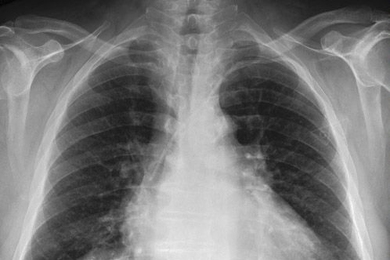

A study of prostate cancer finds “aneuploid” tumors are more likely to be lethal than tumors with normal chromosome numbers.